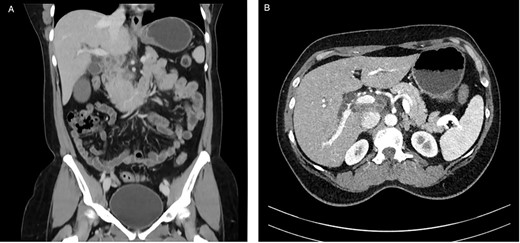

In a previous healthy 41-year-old male with a 3-month history of abdominal pain, fever, fatigue, night sweats and weight loss of 5 kg, a computed tomography (CT) of the abdomen revealed a mechanical ileus due to suspected distinct peritoneal carcinomatosis in the entire abdomen of an unknown primary (Fig. 1).

CT with contrast (A) coronal view and (B) axial view: cystic solid mass in the region of the hepatic hilus with unclear association to the head of the pancreas.